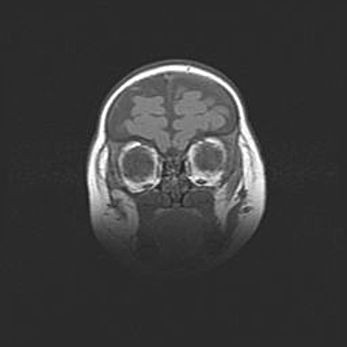

Мальформация Денди-Уокера. Киста задней черепной ямки.

Агенезия мозолистого тела.

Возраст: 2,5 месяца

Вес: 2420 г

Пол: женский

Окружность головы: 37 см

Срок гестации: 32 недели

Мальформация Денди—Уокера — редкий вид патологии ЦНС, представляющий собой врожденный порок развития каудального отдела ствола и червя мозжечка, ведущий к неполному раскрытию срединной (Мажанди) и латеральных (Лушка) апертур IV желудочка мозга. Для этогно синдрома характерна триада симптомов: гипотрофия червя мозжечка и/или полушарий мозжечка, кисты задней черепной ямки, гидроцефалия различной степени. В 70% случаев порок сочетается и с другими аномалиями головного мозга, в частности с агенезией мозолистого тела.